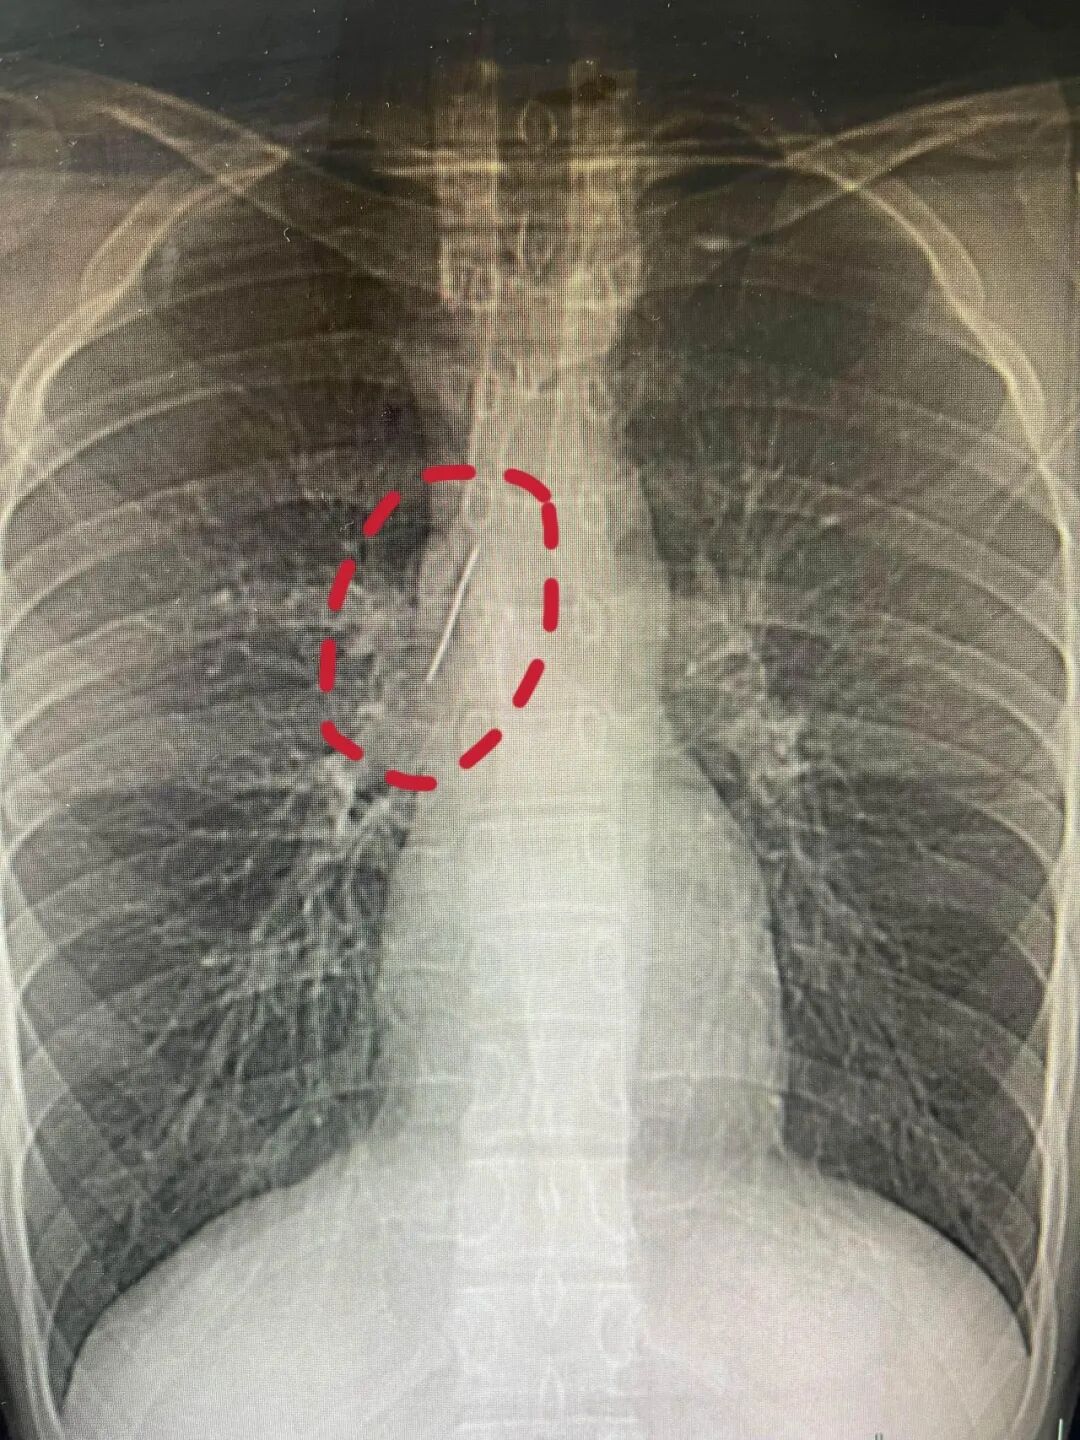

不久前,怀揣军旅梦的他,满怀期待参加征兵体检,没想到胸片结果让医生当场警觉:他的胸腔内有一处明显金属高密度影,形态细长,像一根针。

进一步CT检查确认,异物像是一根金属针,斜插在肺组织内,针尖紧紧贴着胸主动脉、上腔静脉等体内重要血管,稍有位移就可能刺破血管引发致命大出血。

一根5cm长的锈迹斑斑的缝衣针竟悄悄地在他的胸腔深藏多年!这枚针紧贴大血管、刺入肺组织,多年来竟毫无痛感、未发感染、没发生气胸,堪称医学奇迹。